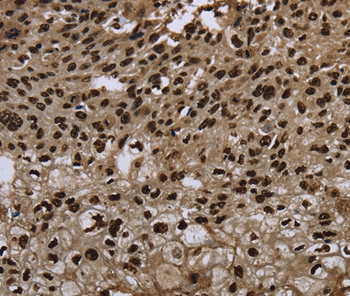

Immunohistochemical analysis of paraffin-embedded Human esophagus cancer tissue using #37693 at dilution 1/20.